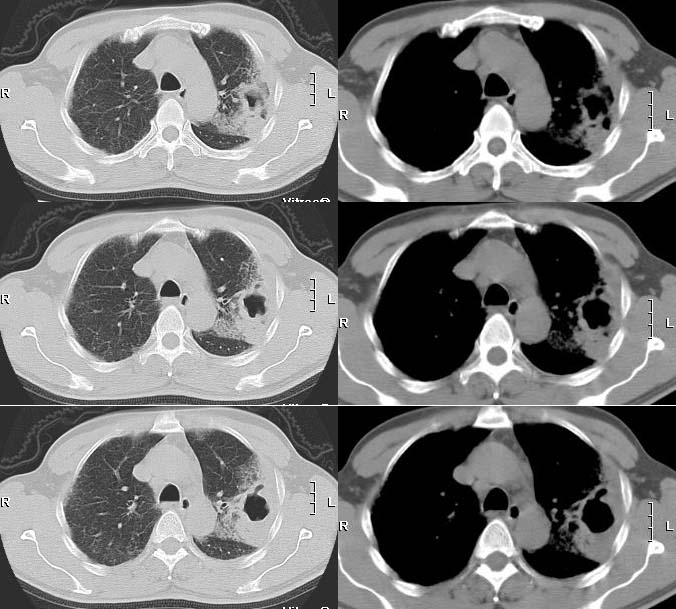

球形肺炎:病变密度相对较淡,中央密度略高,ct图片上密度较为均匀,增强中央可出现无强化区。病变邻近胸膜反应较为显著,可表现为增厚、粘连(可以比较广泛),病变内可以见到大血管的贯穿,周围及近肺门侧可以见到血管纹理增多、增粗,可有支气管充气征象,两侧可垂直于胸膜或呈方形,边缘可为刀切征,它可以出现毛刺样的类似改变,短期内抗炎治疗有效。

炎性假瘤:病灶可呈圆形、椭圆形、三角形、亚铃形等,边缘多比较光滑,密度呈中或偏高密度,周围可有不规则条索影,周围一般无周围充血征象。肿块内可有空洞,可有钙化,但多密度均匀。假性淋巴瘤型可见支气管气相,多为单发,少见多发。肿瘤生长慢,可持续十余年,抗炎可有效果,但阴影不易消散。

③球型肺炎:中央密度高边缘较淡,呈晕样改变;广泛胸膜增厚;病灶呈方形,周围可见斑状、薄片影,周围血管纹理多、增粗,无僵直和牵拉;临床上有起病急变化快,抗炎治疗效果明显,病程短等特征。